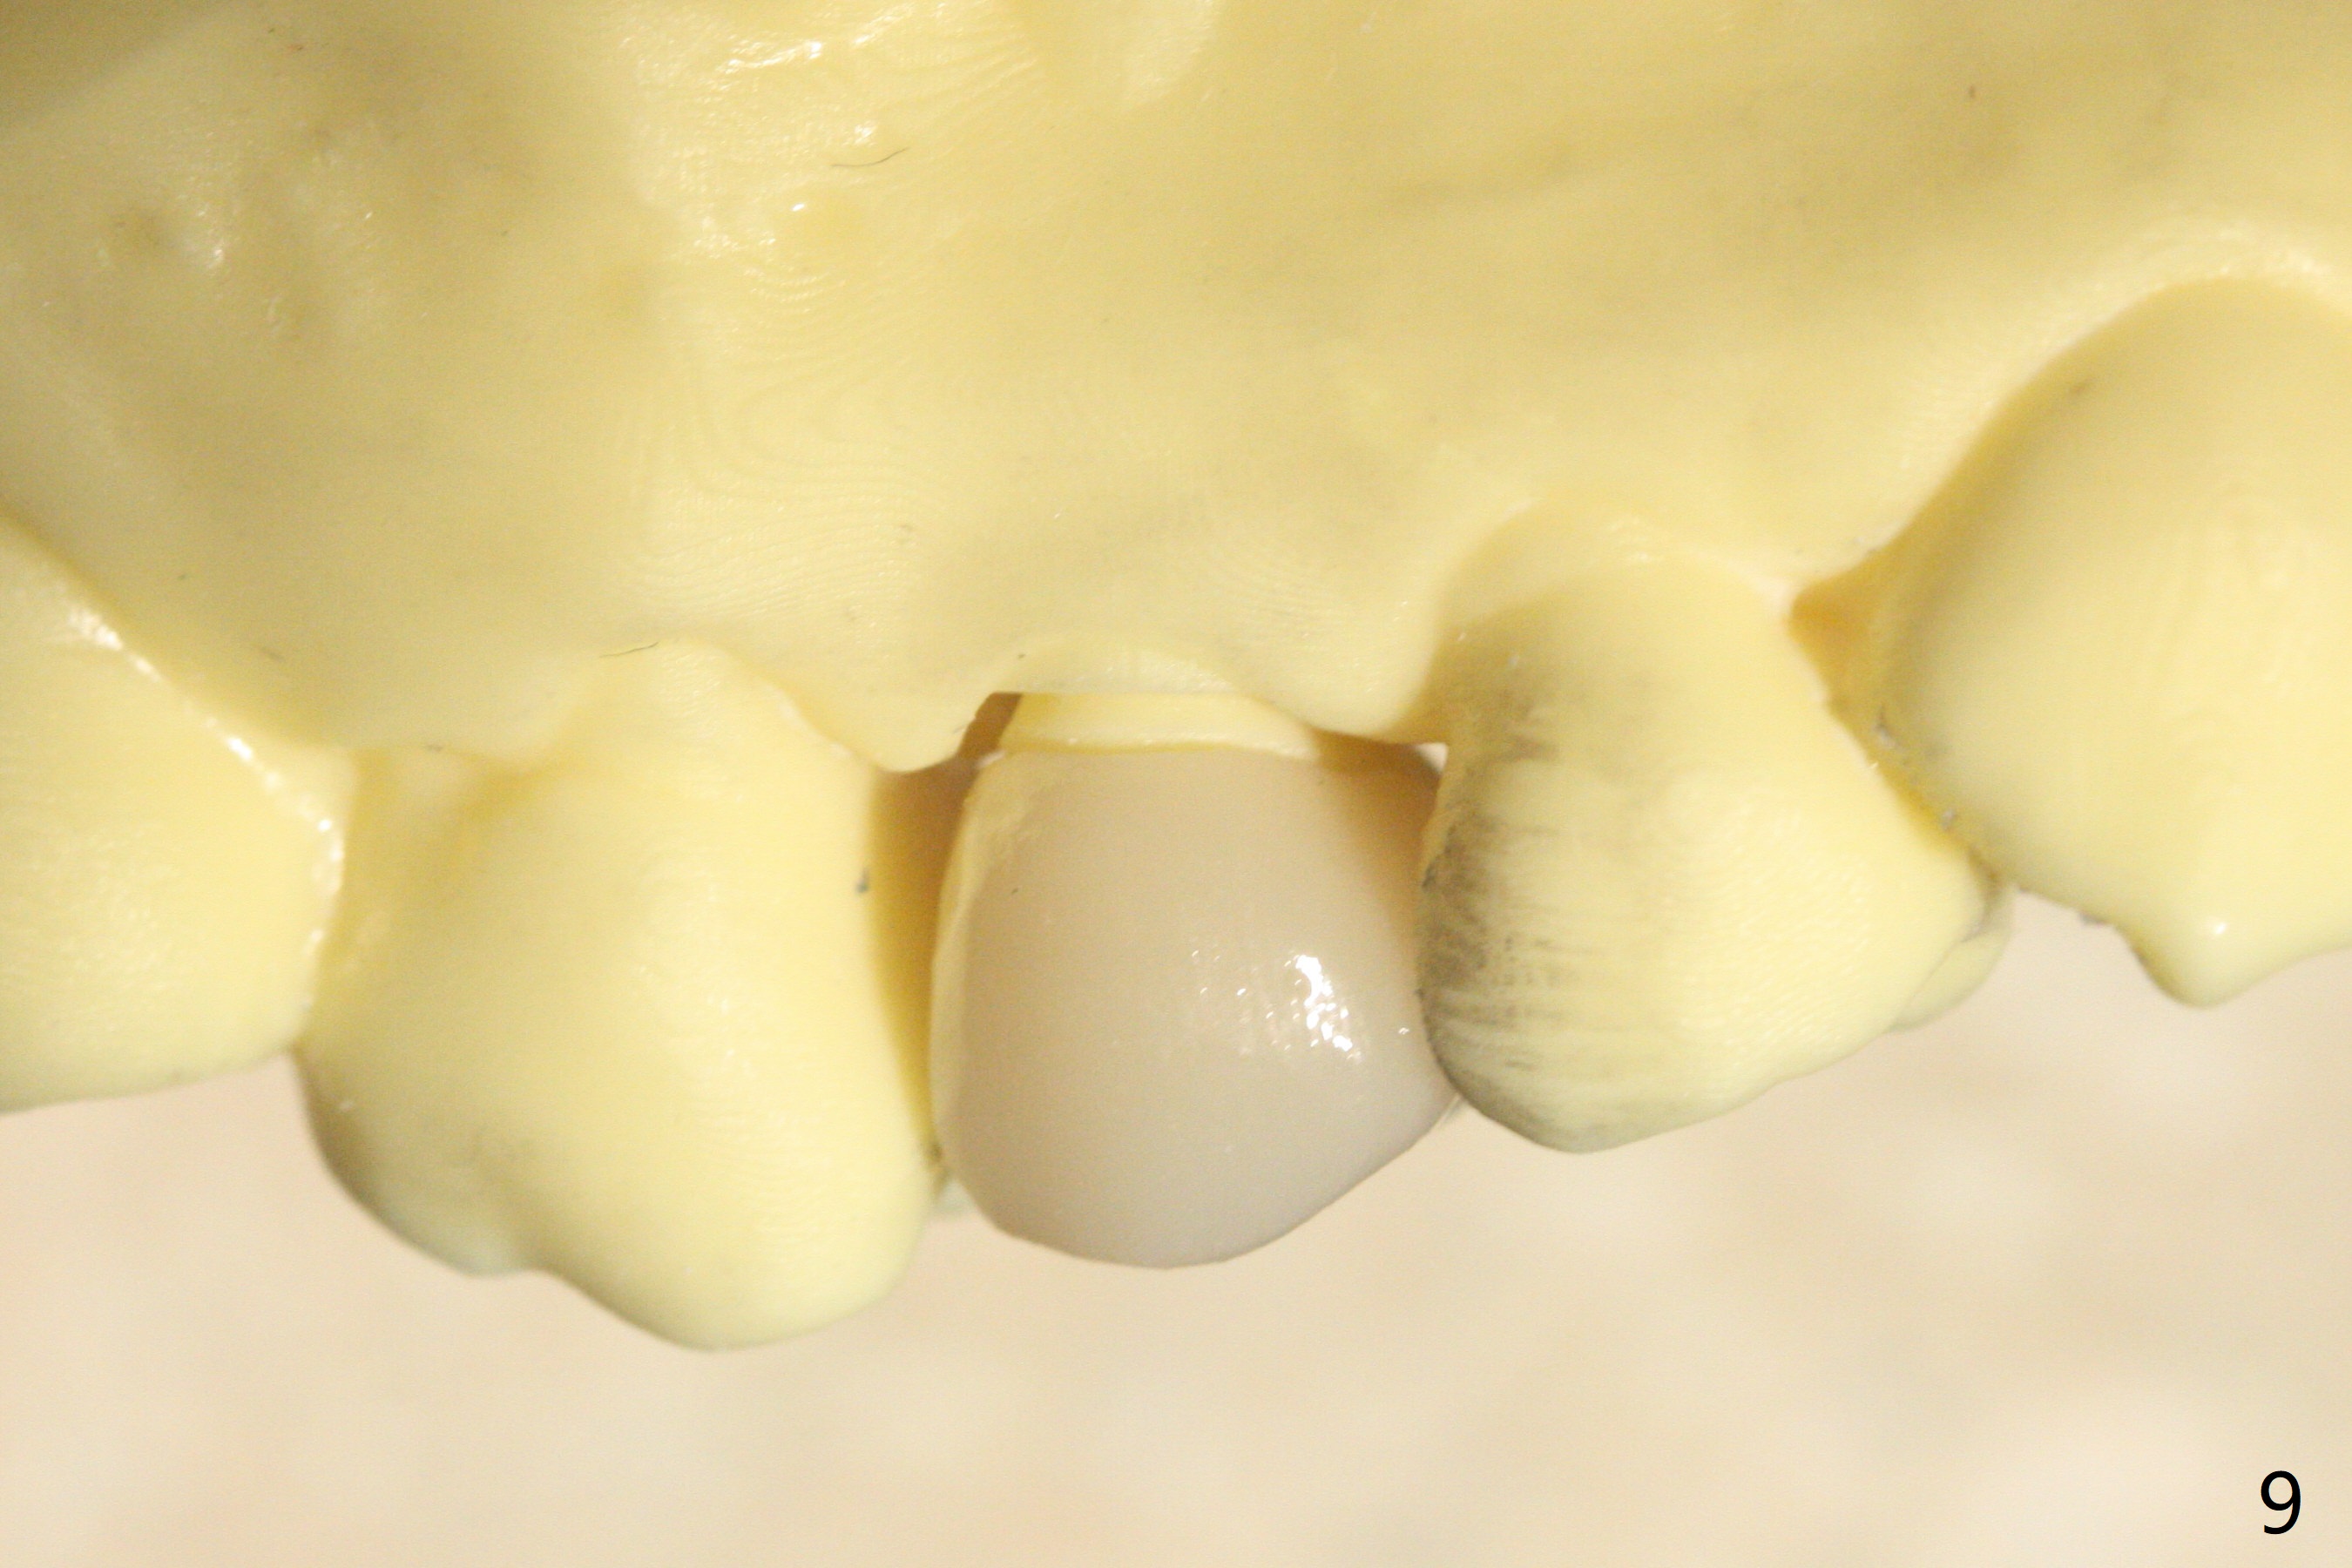

52岁女去年在外州开始4号牙根管治疗(图一),由于新冠病毒和搬家而拖延治疗,现在要求完成根管治疗(图二,三),B: 颊侧(主牙胶尖:20/.04);L: 舌侧(旋转锉:20/.04)。Shining口扫(图四(咬合面观),五(舌侧观),六(颊侧观;对合:局部托牙 (RPD)))。为了保险起见,要求实验室制作两个牙冠:取模,口扫。帮助实验室建立完善数字化系统,从而帮助临床工作。备牙边缘清晰(图八)。牙冠边缘与数字模型(图九)和牙齿吻合,天衣无缝。

Root canal therapy (RCT) was initiated for the tooth #4 of a 52-year-old lady out of state approximately 8 months earlier (Fig.1). The patient requested finishing the treatment and permanent crown fabrication. The buccal (Fig.2 B (master cone 20/.04)) and lingual (L (rotary file 20/.04))) canals fuse near the apex. RCT was done with insertion of 20/.04 and 20/.06 master cones in the buccal and lingual canals, respectively, followed by composite build-up (Fig.3). With basically shoulder margin (not feather margin, chamfer margin ok), it is easy to scan (Fig.4-6 (RPD: removable partial denture)). Return to Oral Scanner Xin Wei, DDS, PhD, MS 1st edition 06/05/2021, last revision 06/25/2021